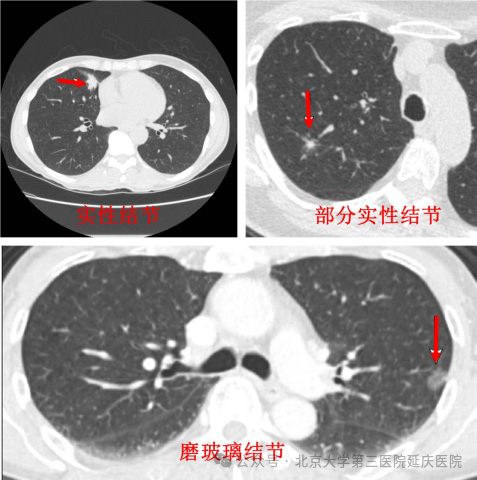

首先要明确,肺结节是肺部影像学检查中发现的直径≤3厘米的局灶性、类圆形密度增高阴影,并非独立疾病。其成因多样,最常见的是炎症愈合后留下的“疤痕”,如肺炎、肺结核治愈后的纤维化结节;其次是良性肿瘤,如错构瘤、脂肪瘤等;少数情况下可能是肺癌的早期表现。2025年《中国肺结节诊治指南》特别强调,不能仅凭“有结节”就判定恶性,需结合多维度特征综合判断。

3.密度方面,混合磨玻璃结节因含有实性成分,恶性概率(约30%-50%)远高于纯磨玻璃结节(约10%-20%)和实性结节(约7%-10%)。